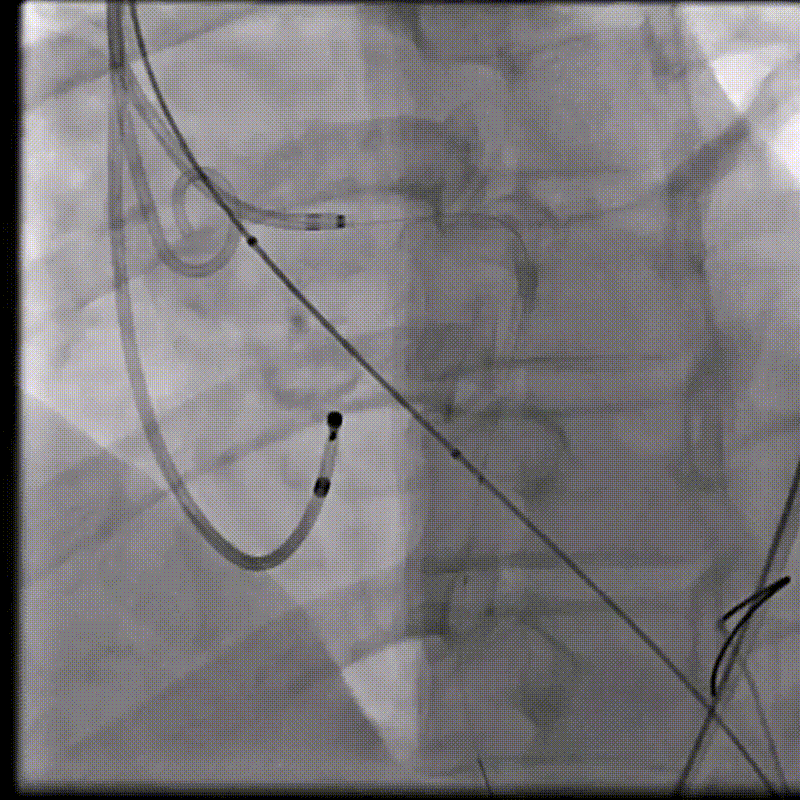

(1)Type 0二叶式主动脉瓣,瓣环适中,中度钙化,Type 0二叶瓣受瓣口形态及钙化影响,瓣架呈非理想椭圆形展开,对瓣架支撑力与顺应性提出了更高要求,同时该病例合并升主扩张,对同轴性和释放的稳定性提出了更高的要求。因此优先选择支撑性和顺应性兼具的瓣膜,以及较柔软花冠的瓣膜,降低对升主动脉的损伤,小锥角的设计进一步提升了瓣膜在释放的稳定性

(2)窦部空间较小,左侧瓣叶冗长,且开口位置在短轴平面,左冠冠脉风险较高,优先选择有收腰设计的瓣膜,降低冠脉风险并保留术后足够的VTC

综合病例解剖特点及患者年纪,决定使用第二代可回收的自膨瓣,可回收提高容错空间,为了降低冠脉阻挡风险,决定采用平衡收腰设计的TaurusElite 的瓣膜,先使用大鞘鞘芯进行预扩,然后上20F大鞘。